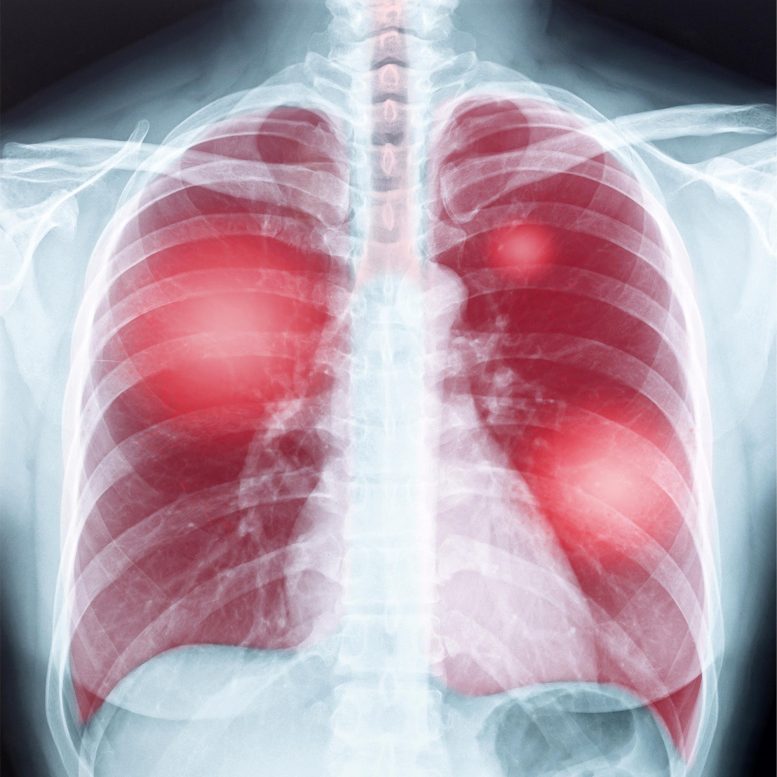

早老の老化または過労幹細胞は慢性肺疾患の重要な要因ですか?発表された研究の結果幹細胞翻訳医学(sctm)これがそうである可能性が高いと言ってください。

以前の研究では、肺細胞の生物学的年齢は、少なくとも2つの慢性肺疾患、特発性肺線維症の時系列よりも大きいことも実証されています(IPF)および慢性閉塞性肺疾患(COPD)。 「これらの研究では、加速老化が新規肺疾患プロセスとして特定されました。しかし、この情報を使用して患者を治療するための新しい治療法を開発するには、時系列の老化と生物学的年齢を増加させる要因をよりよく理解する必要があります」とレイノルズ博士は言いました。それがこの最新の作品の目標でした。